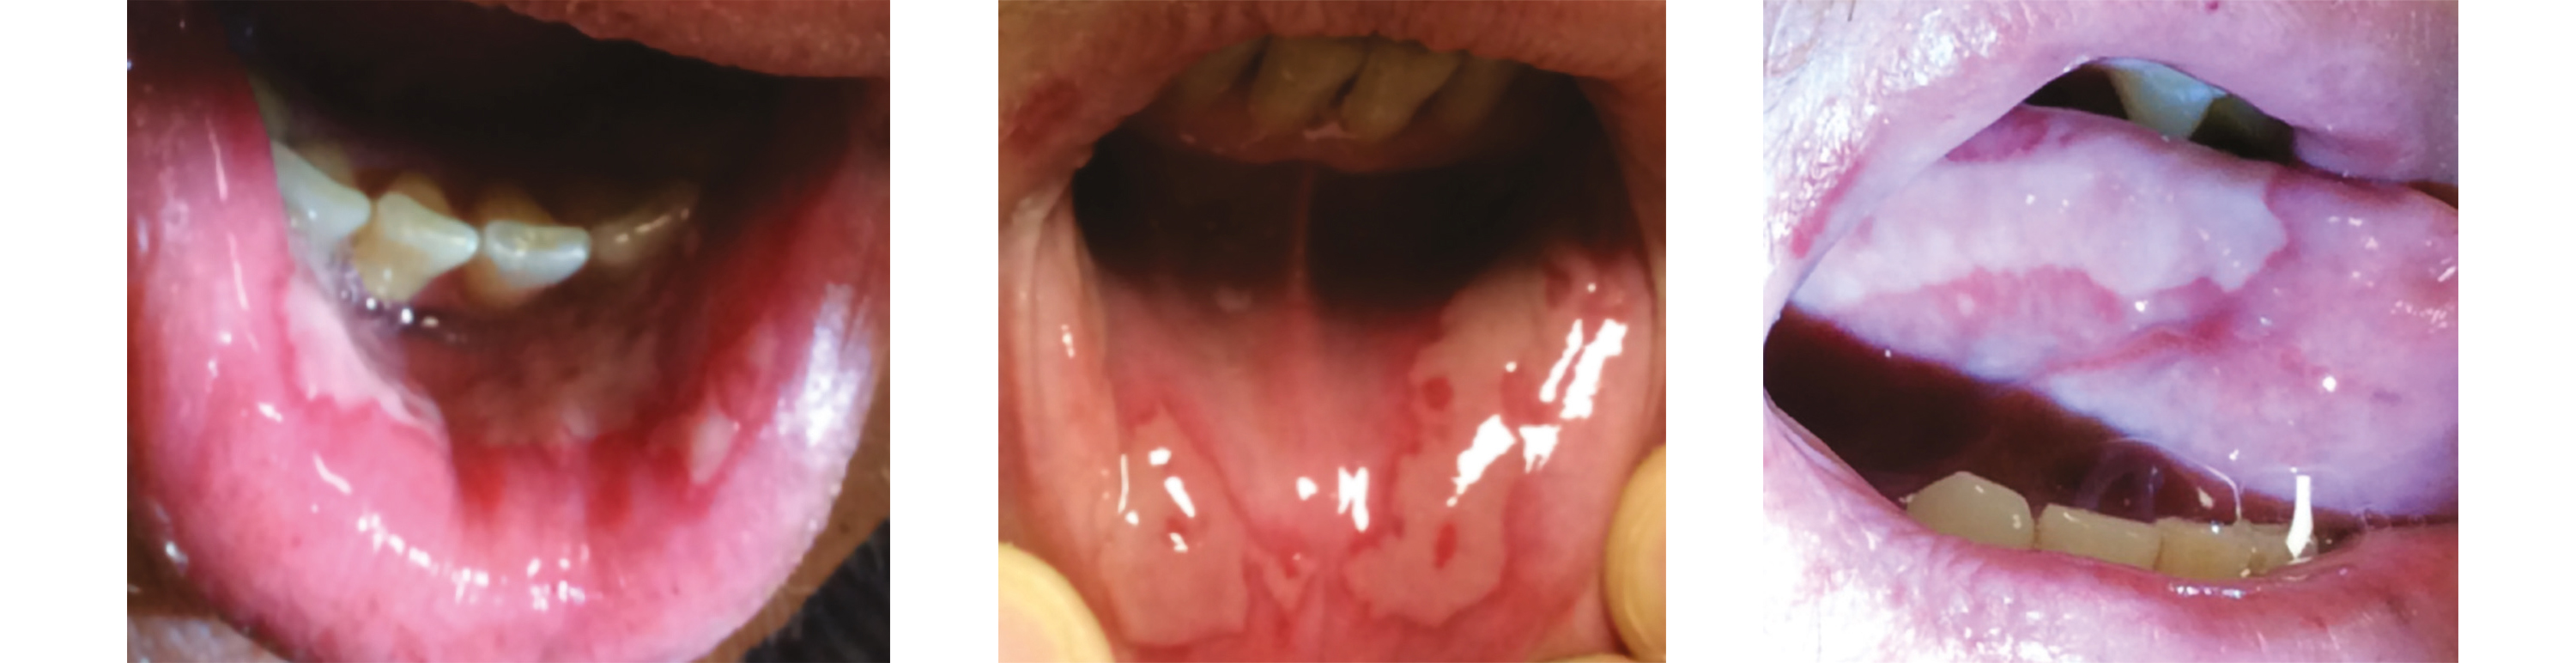

À la 10e séance, une mucite de grade 2 avec aphtes et dysgueusie est constatée lors du suivi IPA, justifiant l'introduction d'un traitement antalgique de palier 1 et 2. Des conseils diététiques personnalisés sont également donnés en collaboration avec la diététicienne. Une xérostomie de grade 1 est notée et la photobiomodulation est intensifiée à visée curative.

Lors de la 14e séance, l'aggravation des symptômes — mucite de grade 3, dysgueusie, xérostomie sévère et odynophagie persistante malgré le traitement morphinique — conduit à l'hospitalisation du patient pour la pose d'une SNG, l'instauration d'une nutrition entérale, un ajustement de l'antalgie, une réhydratation et l'organisation du retour à domicile avec un prestataire de santé et des passages infirmiers quotidiens.

Par la suite, les besoins en soins de support sont réévalués de façon plurihebdomadaire grâce à l'alternance du suivi entre médecins, IPA et manipulateurs lors des séances de photobiomodulation. Cela conduit notamment à l'instauration d'une hydratation intraveineuse avec traitement anti-émétique à domicile, à l'adaptation des traitements antalgiques morphiniques, et au suivi nutritionnel. Le suivi des lésions de mucite est documenté par des photographies lors des séances de photobiomodulation.